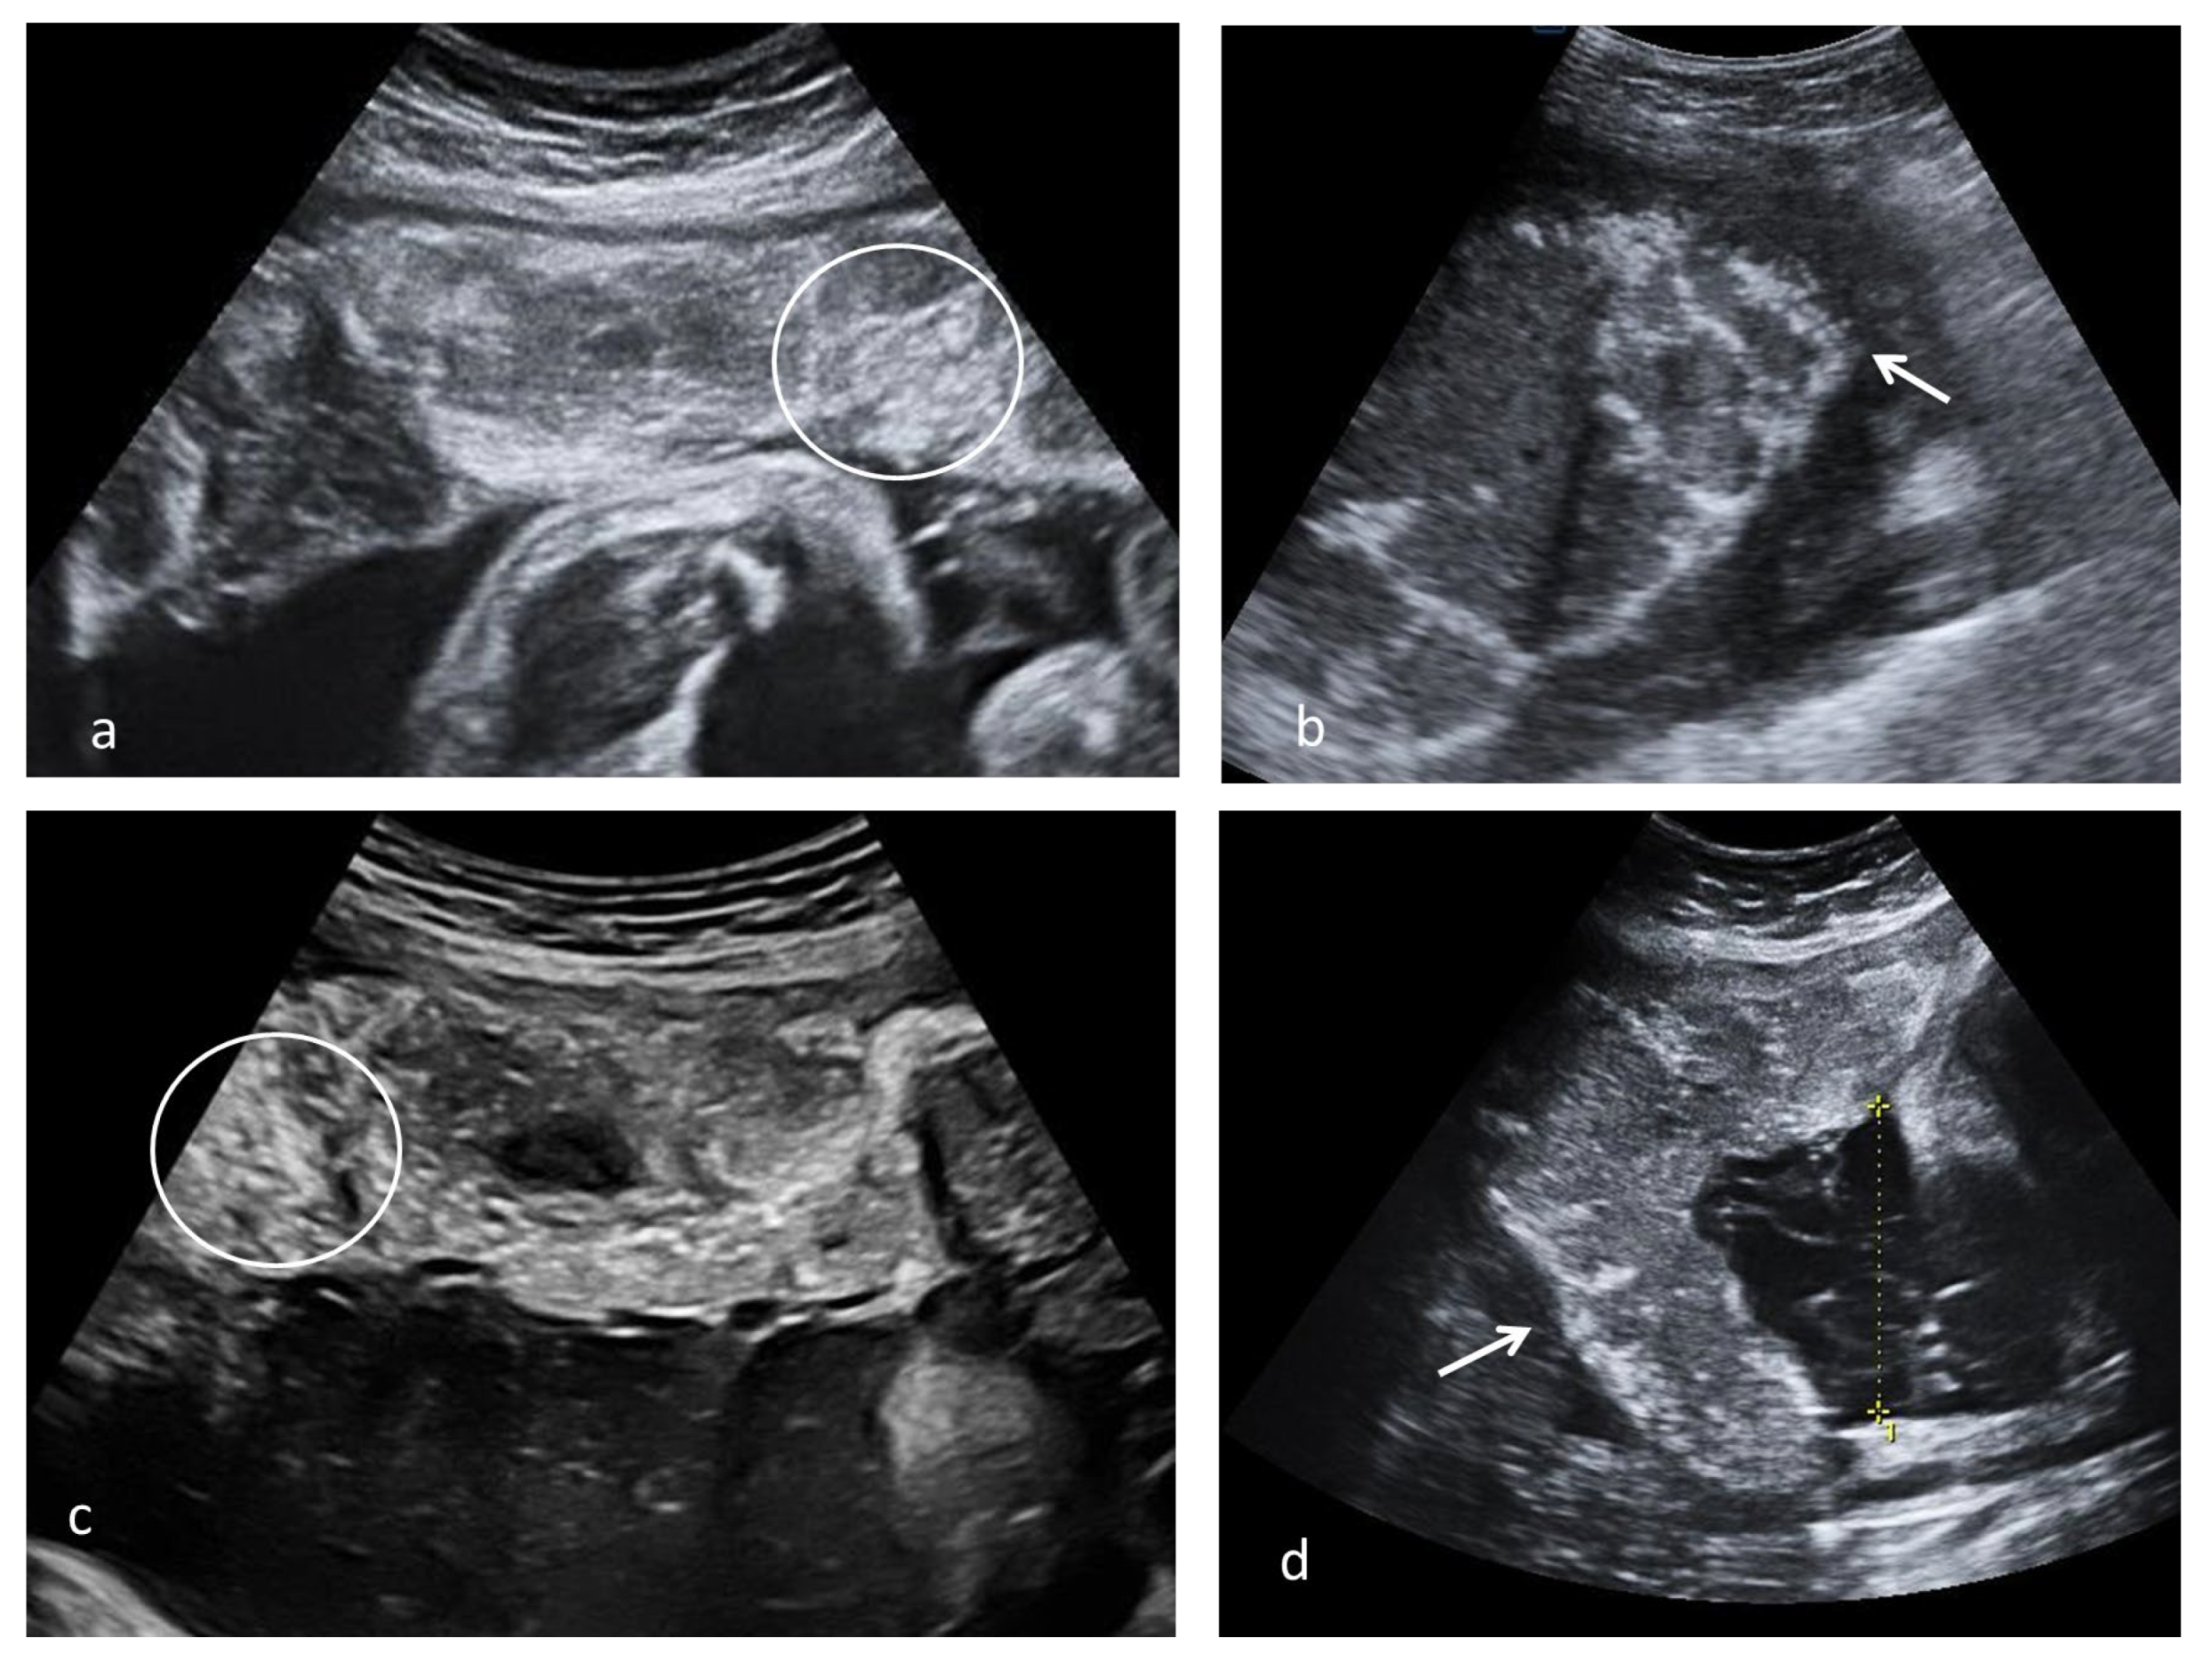

Various aspects of placental remodeling is rendered in Figure 3.

Figure 3.

Placental ultrasound placental aspect observed after SARS-CoV-2 infection; (a) multiple echogenic foci occupying the entire placental volume and the matte glass appearance in 37 weeks of gestation (WG) second para with SARS-CoV-2 infection at 13 WG, natural birth (circle); (b) diffused echogenic foci and continuous white basal line (arrow) in a 39 WG primigravida with SARS-CoV-2 infection at 20 WG, natural birth; (c,d) multiple echogenic foci occupying the entire placental volume (circle), hypoechoic lacunae and white line (arrow) in a 38 WG primigravida with SARS-CoV-2 infection at 26 WG, caesarian section due to intrapartum fetal distress.